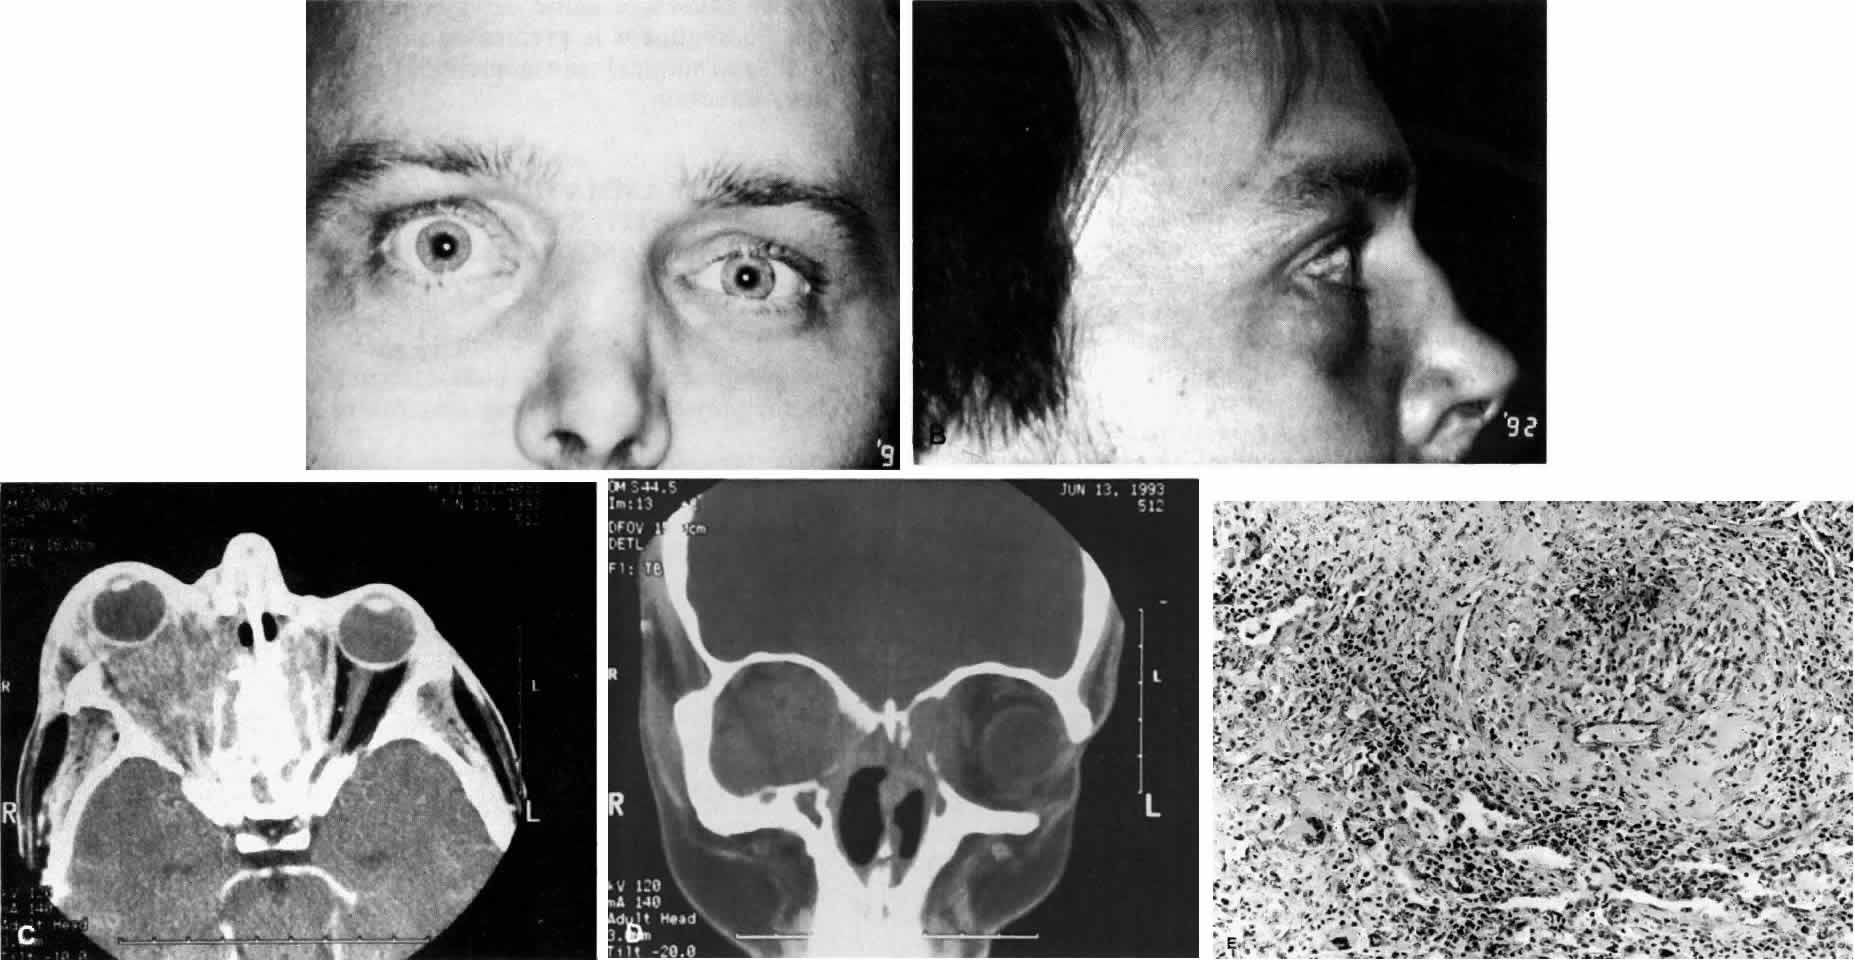

Wegener's granulomatosis is characterized by inflammatory lesions of the upper respiratory tract, lower respiratory tract, the kidneys, and, to varying degrees, generalized small vasculitis of other structures, including the eye (Figs. 10 AND 11). The definitive diagnosis is confirmed by biopsy. A limited form of the disease has been described that spares the kidneys.

Fig. 11. A. This 31-year-old man has had Wegener's granulomatosis for 2 years. His disease process is stable on chronic corticosteroid therapy. He has no evidence of systemic disease. Note right-sided proptosis and hyperglobus. B. Profile of same patient demonstrating collapse of nasal bridge from bony destruction secondary to Wegener's granulomatosis. Note presence of swelling in lower eyelid. C. Axial CT image from the same patient demonstrating significant bilateral disease and bony destruction. Despite the extent of the orbital process on the right, the patient does not have diplopia. D. Coronal CT image showing destruction of medial orbital walls, vomer, and orbital septum. E. Pulmonary biopsy specimen from patient with orbital signs contains an almost obliterated vessel to right of center and scattered giant cells on left (H&E, ×160).

Ocular manifestations include orbital inflammation, scleritis, keratitis, and uveitis. The ocular involvement can occur from extension of sinus and nasal lesions or from focal small vessel vasculitis.